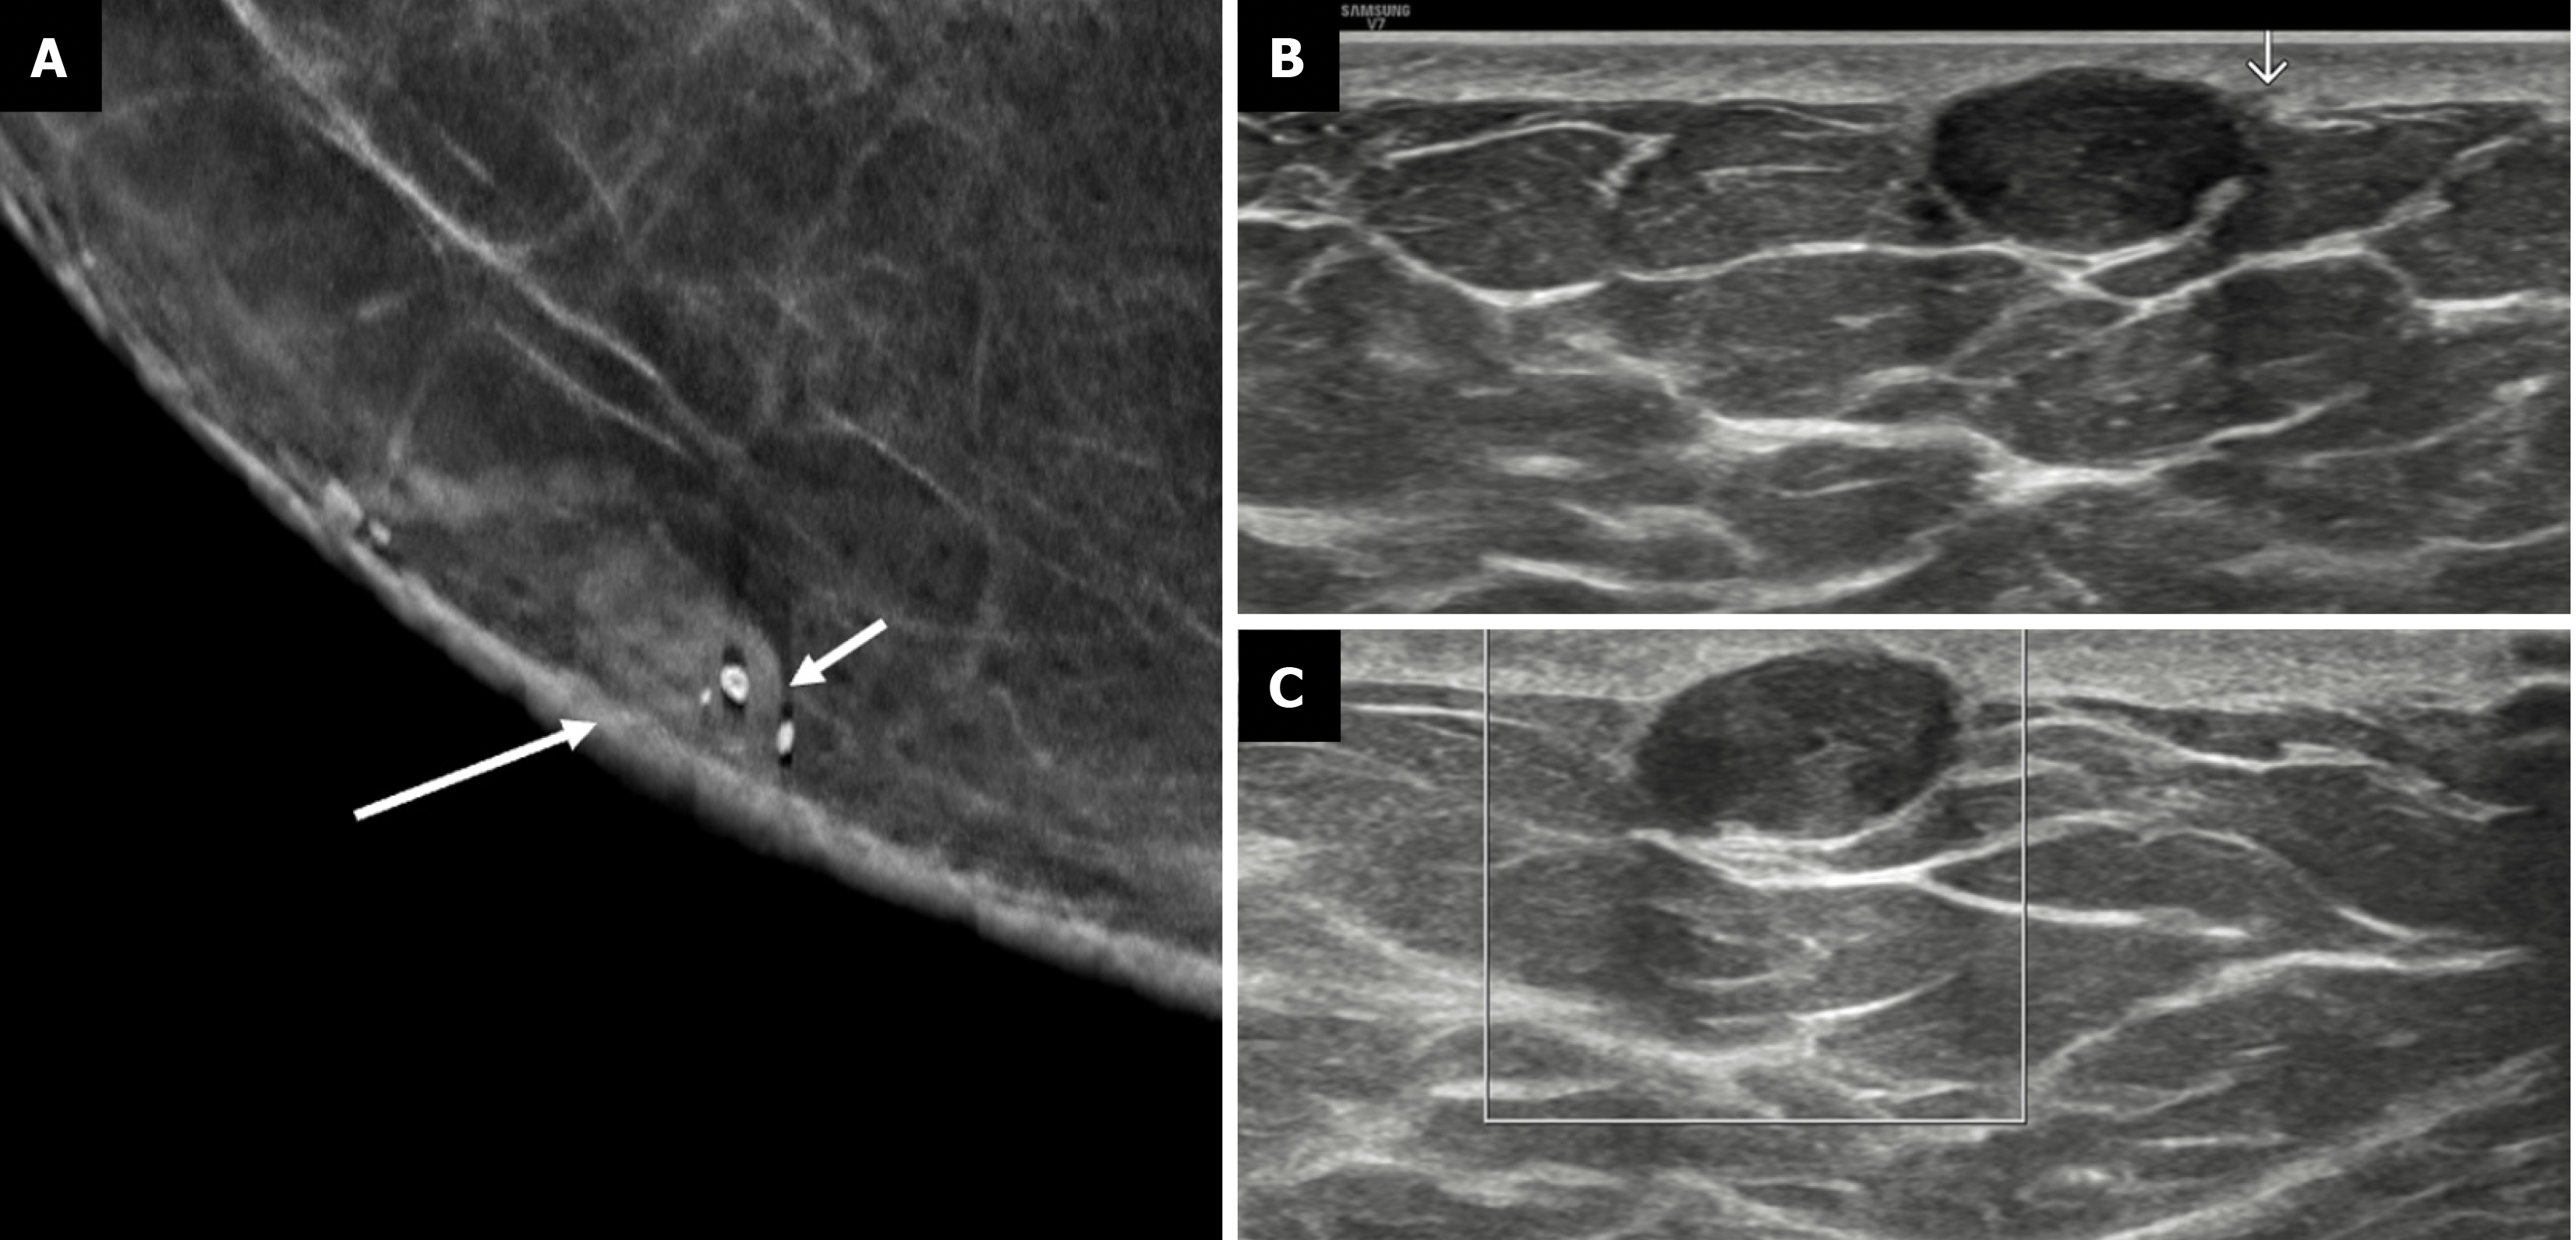

Figure 4 Nodular gynecomastia in a 62-year-old male with tender subareolar masses in bilateral breasts.

A: Mediolateral oblique; B: Craniocaudal mammography views show oval equal density masses in the retroareolar locations of both breasts (white arrows); C-E: Ultrasound images [C, D (color Doppler) and E (panoramic views)] demonstrate an oval parallel indistinct hypoechoic area (denoted by asterisks) in the retroareolar location with no evident vascularity, which is consistent with gynecomastia.